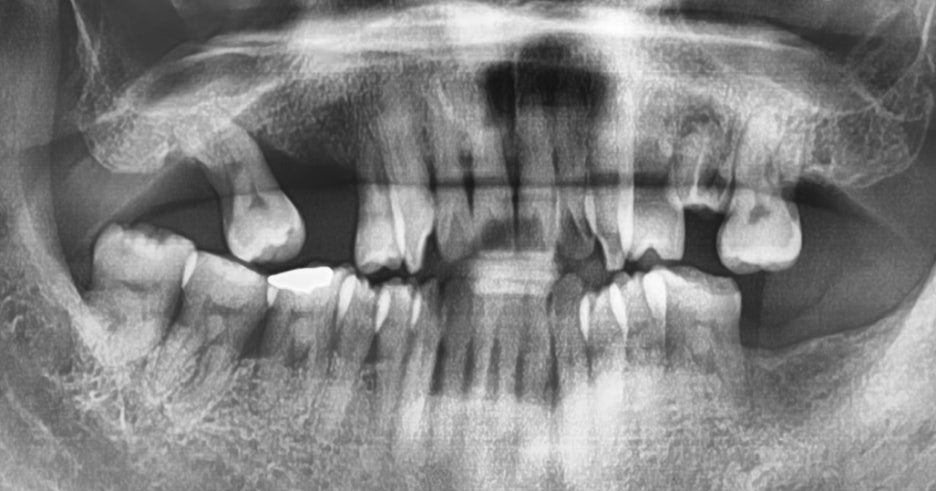

근데 문제는, 남아있는 치조골의 양입니다. 뼈가 이미 많이 얇아진 상태라서

상악동 거상술 은 필연적으로 진행을 해야 되는 상황이며, 이 내용을 환자께도 그대로

안내를 드렸었습니다.